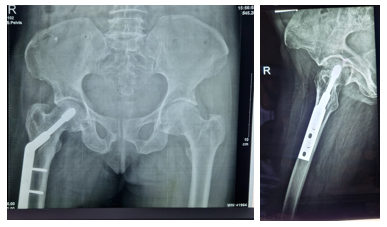

This is a retrospective study of 121 adult patients who had DHS screw fixations on account of proximal femoral fractures within 3 years period (from June 2015 to May 2018). The study site was Orthopaedic Hospital Wamakko, located in Sokoto, North-western region of Nigeria. Formal ethical approval with Ref no. SMH/1580/V.IV was obtained from the Ministry of Health, Sokoto, Nigeria before embarking on the study. Patients’ records were retrieved and data was collected using a self-administered questionnaire and further information was collected during the outpatient clinic visits. The inclusion criterion was hip fractures (Cervical, Intertrochanteric and subtrochanteric) in adult patients with complete records and a minimum of 6 months follow-up. The exclusion criteria were fractures in children, open fractures, neglected fractures for more than 4 weeks, associated hip dislocation, and femoral head and acetabular fractures. There were initially 162 patients included in the study but due to incomplete records, 21 were excluded and 121 patients were included among the study subjects. The relevant demographic data, duration of fracture, injury mechanism, fracture position and type (Figure 1A & 2A), associated fractures and co-morbidities, the interval before surgery, and Parker mobility score were recorded. Descriptive statistics was employed to present our data and the outcomes of the study.

Figure 2 A) 70-year-old woman with a displaced right intertrochanteric fracture following fall 2 weeks prior to presentation. B) Intraoperative fracture reduction and fixation with DHS.

The patient was positioned supine on a traction table and was given either spinal or general anaesthesia. All patients had a single injection of prophylactic 3rd generation Cephalosporin 30 minutes before skin incision as per unit protocol. The fracture was first reduced using image intensification guidance, with the use of traction and slight internal rotation. The presence of smooth medial and anterior cortical bony buttressing on the image indicates satisfactory reduction. An attempt was made to avoid varus mal-alignment of the neck-shaft angle. For patients with late presentation or fracture that could not be reduced using the closed reduction method, the fracture was reduced after opening the fracture site through a lateral approach to the proximal thigh. When the bone was reached and exposed, a guide wire was inserted parallel to the neck after making a small drilled hole which was advanced until the required position and tip-apex distance were obtained (Figure 1B). The pathway of the guide wire was drilled using a DHS triple reamer which was adjusted to the rough length of the DHS screw to be used (Figure 1C). At this stage, tapping may not be necessary, especially in osteoporotic bones. The required screw length (usually 60-95mm) was mounted on the T handle and driven to the appropriate position in the femoral head with the use of intraoperative image guidance (Figure 1D & 2B). The 1350 (4 to 8 holes) DHS side plate was fixed to the screw and a minimum of 2 cortical screws were used to hold the plate in place. Following this, the longitudinal traction was released before the final locking of the locking screw which prevents proximal fragment rotation and further reduced the fracture gap for more stability. Stability was tested by a hip range of motion followed by layered wound closure. In cases of delayed presentation and failure to achieve closed reduction, the fracture site has to be open first to release any fibrous tissue and callus to achieve desirable fracture reduction. This may cause more bleeding and prolong operation time compared to cases with early presentation.